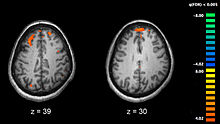

Schizophrenia is associated with subtle differences in brain structures, found in 40 to 50% of cases, and in brain chemistry during acute psychotic states. Studies using neuropsychological tests and brain imaging technologies such as fMRI and PET to examine functional differences in brain activity have shown that differences seem to most commonly occur in the frontal lobes, hippocampus and temporal lobes. Reductions in brain volume, smaller than those found in Alzheimer's disease, have been reported in areas of the frontal cortex and temporal lobes. It is uncertain whether these volumetric changes are progressive or preexist prior to the onset of the disease. These differences have been linked to the neurocognitive deficits often associated with schizophrenia. Because neural circuits are altered, it has alternatively been suggested that schizophrenia should be thought of as a collection of neurodevelopmental disorders.